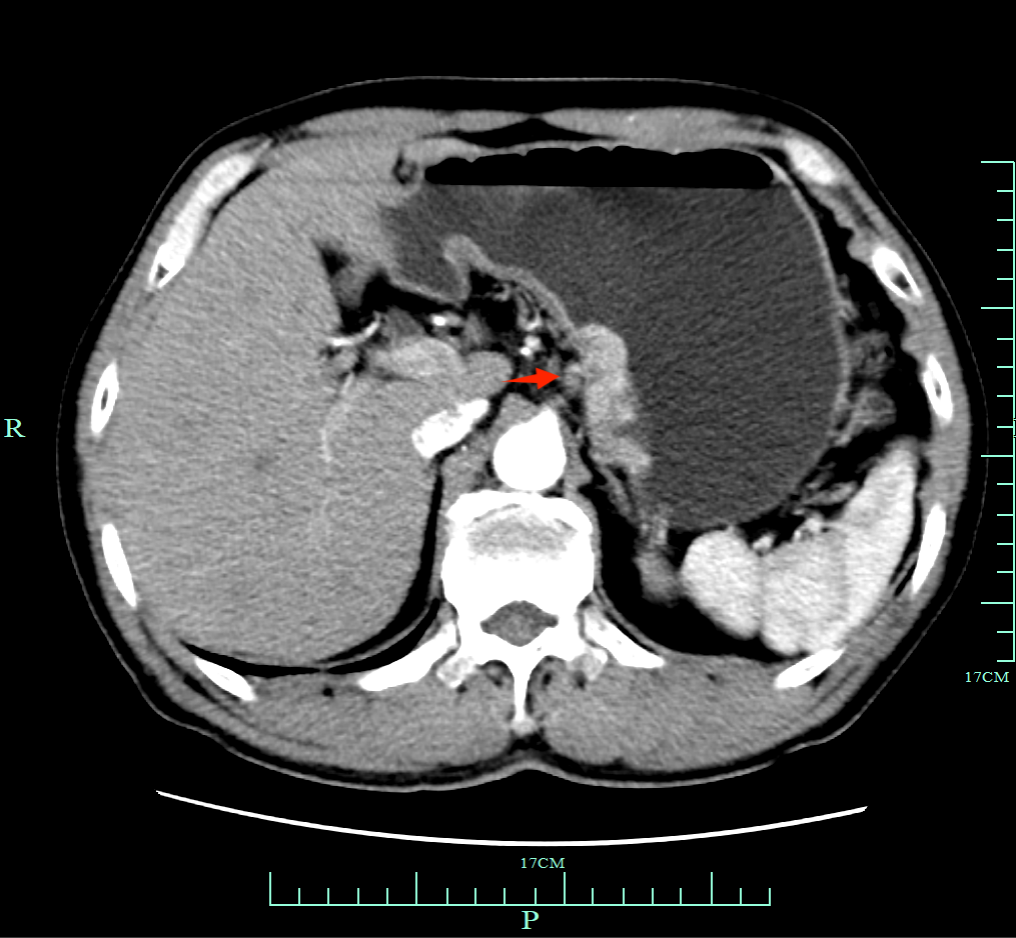

CT检查(2023年6月25日):胃贲门部胃癌,病灶累及范围约4.6cm。

图1 CT检查结果